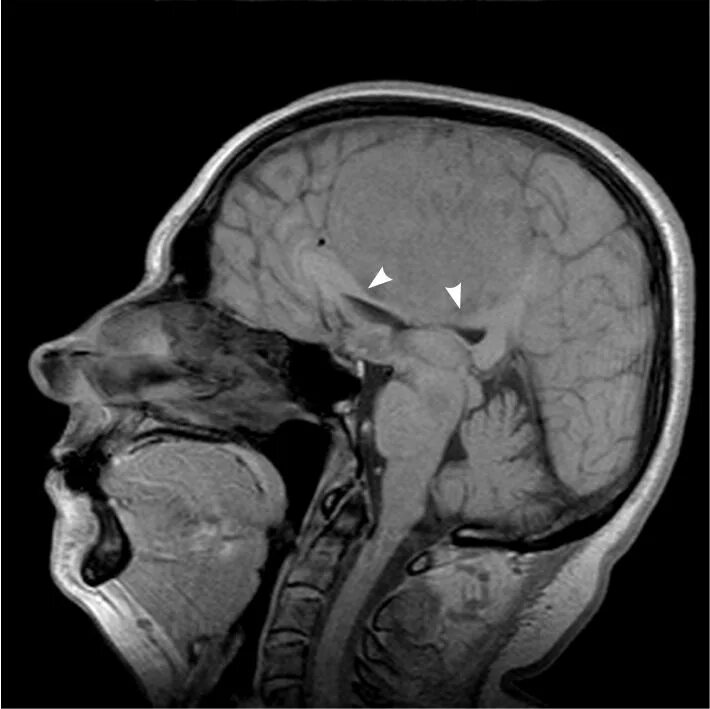

Как выглядит опухоль на снимках